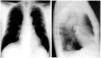

Fig. 1. Radiografías de tórax posteroanterior y lateral que muestran una masa de 3 cm en lóbulo inferior izquierdo y nódulo de 1,5 cm en lóbulo superior izquierdo.